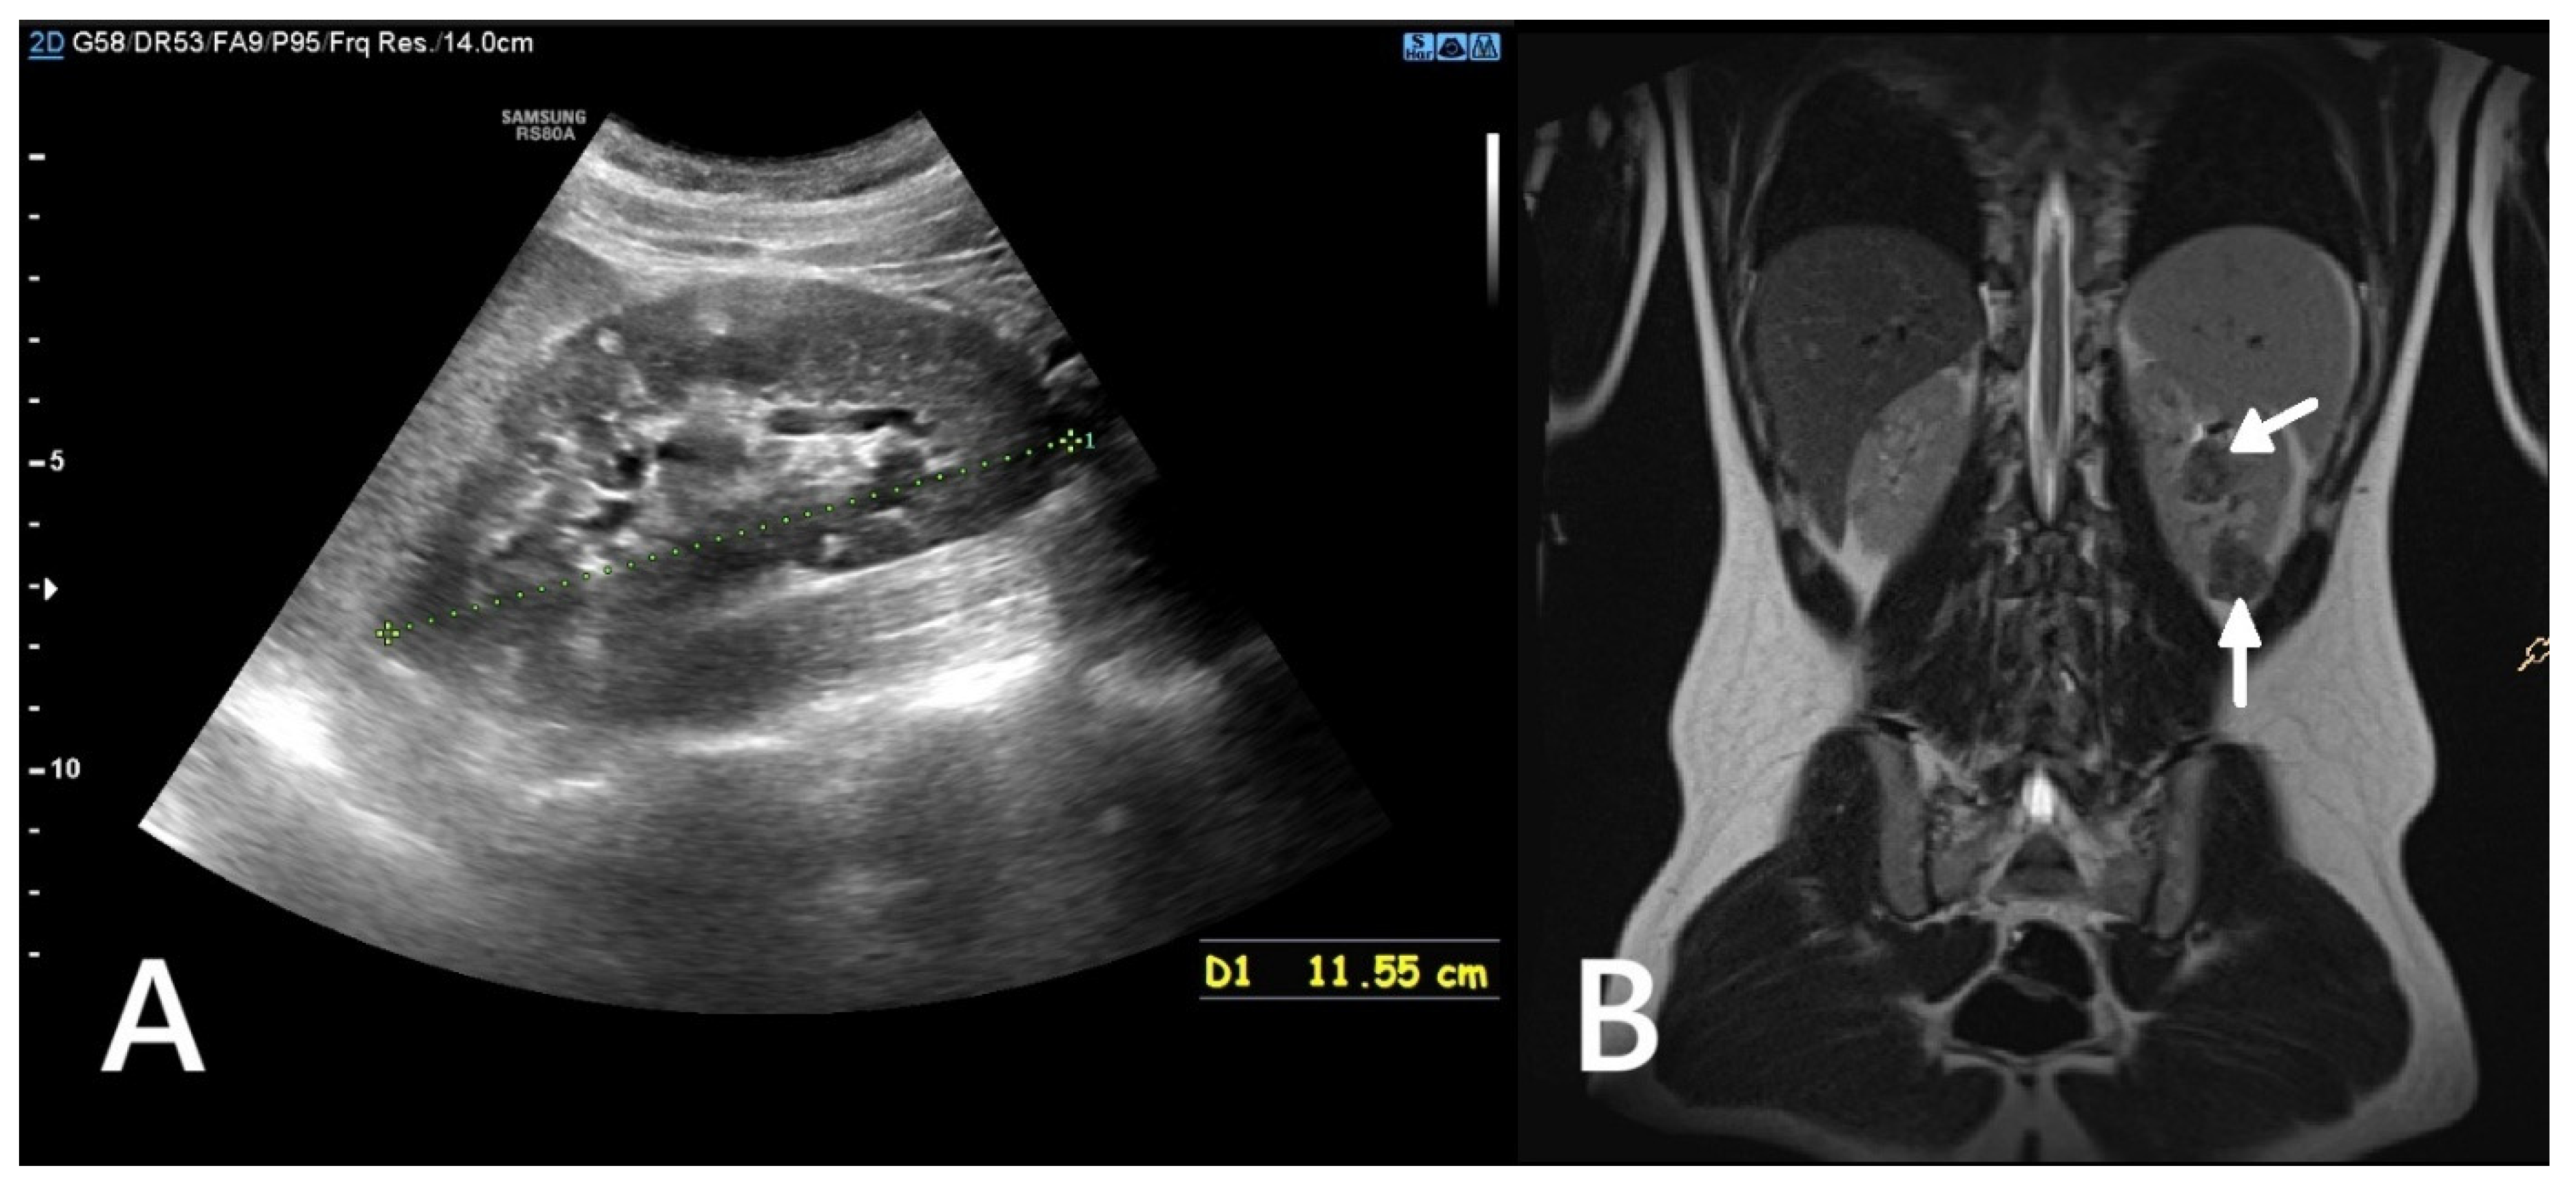

Potential complications of AML include haemorrhage (Wunderlich syndrome), the risk of which increases with the size and vascularisation of the lesion (Figure 2), and mass effect, which can cause discomfort or pain and may impair renal function by compressing urinary outflow or distorting normal renal parenchyma [19].

Figure 2. An ultrasound of a 10-year-old girl. A well-defined heterogeneous lesion, likely an AML, extending beyond the outline of the kidney. Within the lesion a fluid-filled area, likely a site of hemorrhage (*).